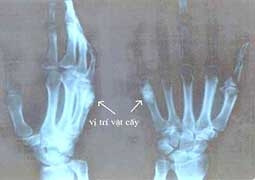

Sau hai đợt thử nghiệm cấy ghép vật liệu trên động vật thành công, nhóm nghiên cứu đã thử nghiệm trên cơ thể người bệnh tại Bệnh viện Tai - Mũi - Họng Trung ương, Bệnh viện Bạch Mai, Bệnh viện Răng - Hàm - Mặt Trung ương, Bệnh viện K với nội dung: sử dụng vật liệu để thay thế các chi tiết chuỗi xương tai truyền âm thanh; thay các chi tiết xương tai giữa; thay chân răng và sửa chữa xương hàm mặt; hàn vá phần xương bị khoét bỏ.

Trong tất cả các ca phẫu thuật cấy ghép vật liệu gốm thủy tinh y sinh cho người bệnh, không có trường hợp nào có phản ứng đào thải. Bệnh nhân chóng lành vết thương, khả năng hồi phục sức khỏe tốt, đặc biệt khả năng khôi phục chức năng của bộ phận điều trị rất cao.